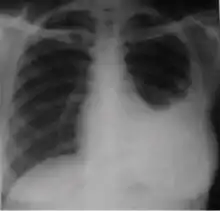

4. Pleural effusion - Presence of a significant amount of fluid within the pleural space. This finding must be distinguished from blunting of the costophrenic angle, which may or may not represent a small amount of fluid within the pleural space (except in children when even minor blunting must be considered a finding that can suggest active TB).

Chest x-ray showing dense opacity pleural effusion in the lower left lung of primary pulmonary TB.